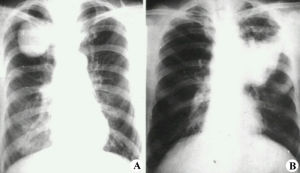

3、X線檢查X線特點為均勻緻密陰影,占據一側胸部、一葉或肺段。陰影無結構,肺紋理消失及肺葉體積縮小。一側或大片肺不張時可見肋間變窄、胸腔縮小。陰影位置隨各肺葉肺不張的部位而異。下葉肺不張在正面胸片中成三角形陰影,位於脊柱與膈肌之間,在側片中則靠近後胸壁。若繫上葉肺不張,則正面、側面影均呈楔形,其尖端向下並指向肺門。若系右側中葉的肺不張,其正面陰影呈三角形,底部位於心影的右緣,尖端指向外側;其側影為一楔形,底部近前胸壁,位於膈肌之上,尖端向後及向上。在幼嬰時期,除代償性肺氣腫之外,其他代償現象如氣管與心臟移位及膈肌上升,可暫不出現,直至肺不張持續較久後才發生。但由於表面活性物質不足造成的微型肺不張,肺多呈毛玻璃狀陰影,X線表現與小葉肺炎無異。4、病程梗阻性肺不張可以短暫或持久。肺炎、毛細支氣管炎、哮喘及支氣管炎所致粘液栓塞或黏膜水腫而形成的肺不張,時間較短,消炎去腫後即易消失。由於結核病或未取出的異物時,肺不張可較持久。雙側或大面積肺不張常迅速死亡,應立即用支氣管鏡吸出堵塞物,並進行人工呼吸搶救才可存活。

肺不張診斷主要靠胸部影像學檢查、病因,診斷需結合病史。肺不張的X線表現分直接X線徵象和間接X線徵象兩種。

肺不張的直接X線徵象

不張的肺組織透亮度降低,均勻性密度增高,恢復期或伴有支氣管擴張時可密度不均(囊狀透亮區)。不同程度的體積縮小,亞段及以下的肺不張可因有其他側枝的通氣而體積縮小不明顯。葉段性肺不張一般呈鈍三角形,寬而純的面朝向肋膈胸膜面,尖端指向肺門,有扇形、三角形、帶狀、圓形等。

肺不張的間接X線徵象

葉間裂向不張的肺側移位,如右肺橫裂葉間胸膜移位,兩側的斜裂葉間胸膜移位等;由於肺體積縮小,病變區的支氣管與血管紋理聚攏,而鄰近肺代償性膨脹,指使血管紋理稀疏,並向不張的肺葉弓形移位;肺門陰影向不張的肺葉移位;肺門陰影縮小和消失,並且與肺不張的緻密影相隔合;縱隔、心臟、氣管向患側移位,特別是全肺不張時明顯,有時健側肺疝移向患側,而出現縱隔疝;橫膈肌升高,胸廓縮小,肋間隙變窄。